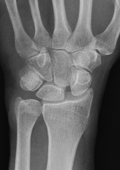

- Zentrum für Orthopädie und Unfallchirurgie

- Traumazentrum